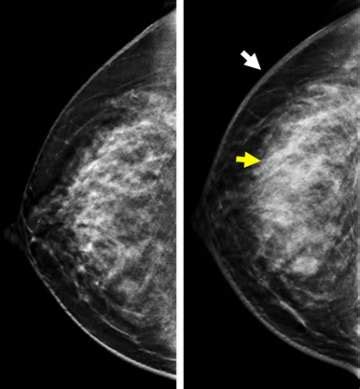

So, why is ultrasound for inflammatory breast cancer such a big deal? Well, traditional mammograms, while excellent for detecting many types of breast cancer, can sometimes miss IBC. This is because IBC often causes diffuse changes throughout the breast, like skin thickening and increased fluid in the breast tissue, rather than a distinct mass. Ultrasound, on the other hand, is fantastic at visualizing these subtle changes. It uses sound waves to create detailed images of the breast’s internal structures. For IBC, an ultrasound can help doctors see:

- Skin Thickening: A hallmark of IBC is thickened skin, and ultrasound is great at measuring and visualizing this.

- Edema (Fluid Buildup): Ultrasound can detect increased fluid in the breast tissue, another common sign of IBC.

- Lymph Node Involvement: It can also help assess the nearby lymph nodes, which can become enlarged if the cancer has spread.

- Vascularity: Advanced ultrasound techniques can even look at blood flow within the breast, and IBC often shows increased vascularity.

Think of it this way: a mammogram is like a general overview, while an ultrasound is like a high-resolution zoom lens that can pick up finer details. This makes it an indispensable tool, especially when a patient presents with symptoms suggestive of IBC. Doctors might order an ultrasound even if a mammogram appears normal, simply because the clinical signs are concerning. The ability of ultrasound to differentiate between solid masses, cysts, and areas of inflammation is also a significant advantage. For IBC, the inflammation and blockage of lymphatics are key features that ultrasound can highlight better than other methods. This detailed imaging allows for a more accurate assessment of the extent of the disease and helps in distinguishing IBC from other conditions that might cause similar-looking symptoms, like benign infections. Ultimately, the goal is to get the most accurate diagnosis as quickly as possible, and ultrasound plays a starring role in achieving that for patients suspected of having inflammatory breast cancer.

Now, let’s get into the nitty-gritty of interpreting inflammatory breast cancer ultrasound results. This is where the radiologist, that specialized doc we just talked about, really earns their stripes. They’re looking for specific patterns and characteristics that are indicative of IBC. As we’ve mentioned, ultrasound for inflammatory breast cancer is key because IBC often presents with diffuse changes rather than a discrete lump. So, what exactly are they scrutinizing on those images?

- Diffuse Parenchymal Enhancement: This refers to increased brightness or signal in the breast tissue on the ultrasound, suggesting inflammation and increased blood flow, which is common in IBC. The radiologist will assess the pattern and extent of this enhancement.

- Skin and Subcutaneous Tissue Thickening: The normal skin thickness is usually just a couple of millimeters. In IBC, this can significantly increase, often exceeding 2-3 mm, and appear irregular. Ultrasound is excellent at precisely measuring this thickness and noting any architectural distortion.

- Edema (Fluid Accumulation): Ultrasound can identify collections of fluid within the breast tissue or in the space between the skin and the breast tissue. This edema is a direct result of the inflammation and blocked lymphatic drainage characteristic of IBC.

- Axillary Lymph Node Assessment: The radiologist will also carefully examine the lymph nodes in the armpit (axilla). In IBC, these nodes can become enlarged and may show abnormal features, suggesting that the cancer might have spread. Ultrasound can guide a biopsy of suspicious lymph nodes if needed.